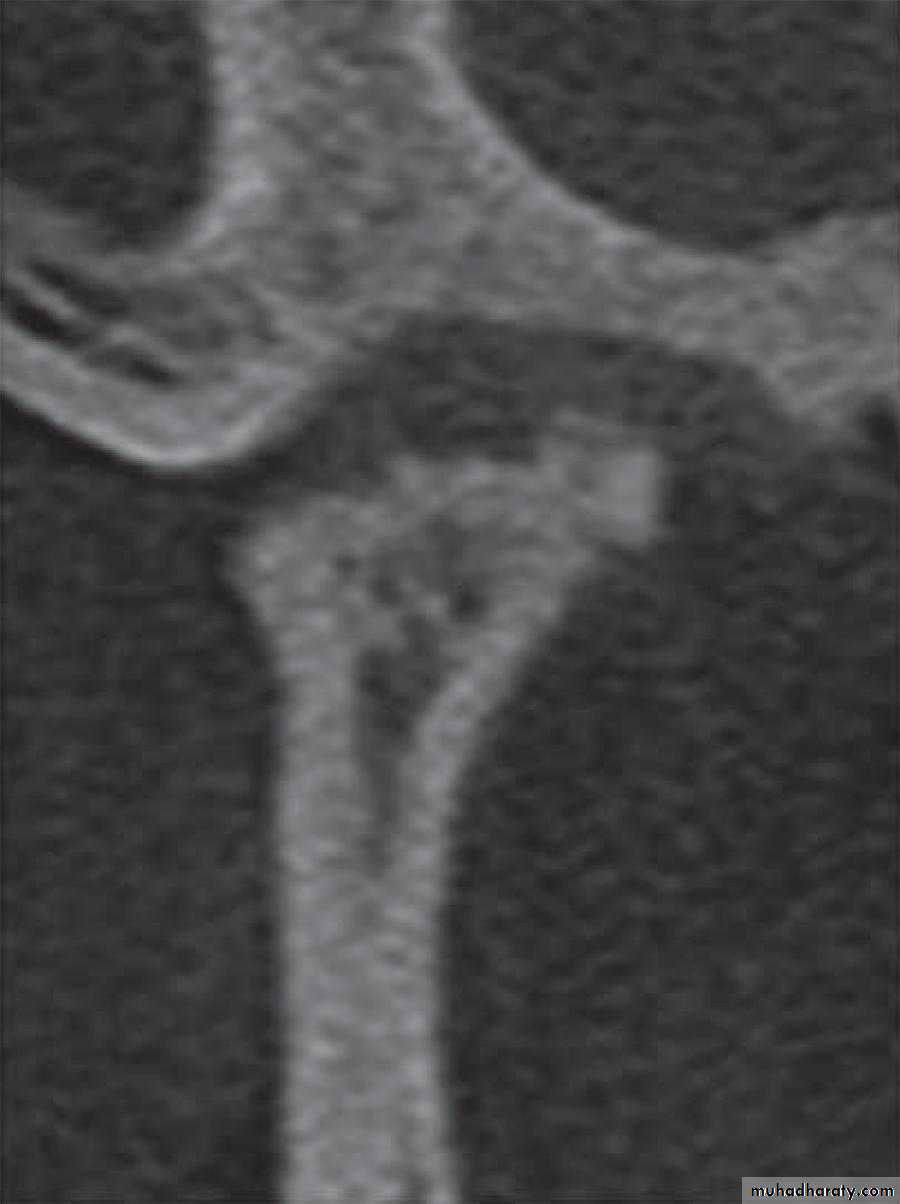

2. Cone-beam computed tomography images (CBCT)

It is usually indicated if bony changes are anticipated like in degenerative joint diseasesRadiology

Radiology

By OPG OR Ct-Scan

It not seen in early changes

1. Erosions of the articular surfaces of the condyle (flattening) and, less commonly seen, of the mandibular fossa.

2. Sclerosis of the bone and marginal

bony proliferation (‘lipping’ or osteophytes).3. Narrowing of the radiographic joint space.

4. Bony proliferations may break away and be seen as loose bodies in the joint space.5. Subcondyle pseudocyst.